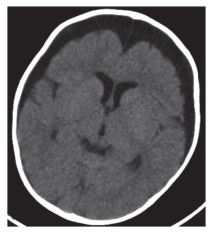

入院时实验室检查结果显示,(1)血常规:白细胞17.9×109/L,中性粒细胞百分比65.9%,淋巴细胞15.2%,血红蛋白69 g/L,血小板82×109/L;C反应蛋白69.60 mg/L;降钙素原13.75 ng/mL;D-二聚体6823 μg/L;(2)肝功能:白蛋白20.0 g/L,丙氨酸氨基转移酶98 U/L,门冬氨酸氨基转移酶58 U/L,氨基末端B型利钠肽前体 > 35 000 pg/mL;铁蛋白1 058.1 ng/mL;(3)入院后腰椎穿刺,脑脊液压力12 cmH2O。脑脊液常规检查:白细胞61×106/L,中性粒细胞16.3%,单核细胞83.7%。脑脊液生化结果:糖4.9 mmol/L,蛋白2.18 g/L。骨髓穿刺未观察到噬血细胞。免疫球蛋白、抗链球菌溶血素O(anti-streptolysin O,ASO)、血细菌培养无异常。(4)影像学检查:胸部CT,双肺多叶段炎症,部分肺组织实变。双侧胸腔积液(图 1A、1B)。颈部淋巴结彩超,双侧颈部淋巴结可见,左侧较大者1.2 cm×0.4 cm,右侧较大者1.1 cm×0.3 cm。头部CT(图 2)及心脏彩超无明显异常。

| A,肺窗;B,纵膈窗. 图 1 患儿入院第1天肺CT |